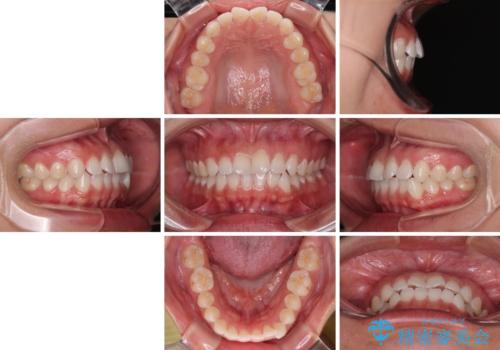

- 上下前歯のデコボコを気にして来院された患者様です。

ワイヤー矯正でもマウスピース矯正でも可能でしたが、短期間で、自身の手を煩わせることなく治療を行いたいとのことで、ワイヤー装置にて矯正治療を行うこととしました。

僅か半年強、あっという間に治療を終えることができました。